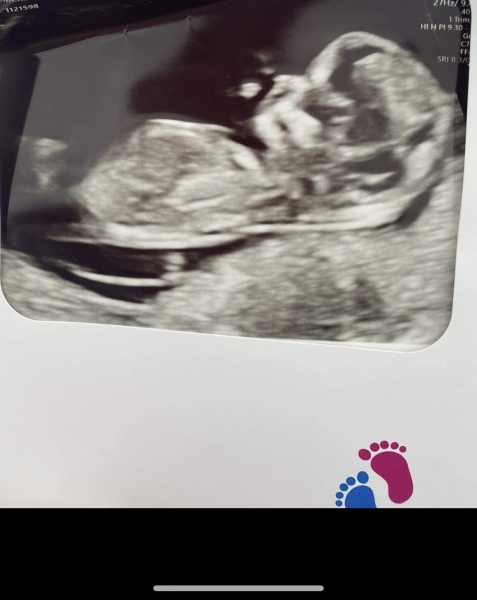

Gender scan

What you recon boy or girl ?)